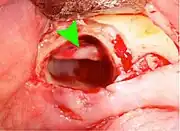

Pericoronitis (green arrow) in lower right wisdom tooth

Impacted wisdom teeth without communication to the mouth, that have no pathology associated with the tooth, and have not caused tooth resorption on the blocking tooth, rarely have symptoms.[11] The chances of developing pathology on an impacted wisdom tooth that is not communicating with the mouth is approximately 12%.[11] However, when impacted wisdom teeth communicate with the mouth, food and bacteria penetrate to the space around the tooth and cause symptoms such as localized pain, swelling and bleeding of the tissue overlying the tooth. The tissue overlying the tooth is called the operculum, and the disorder is called pericoronitis which means inflammation around the crown of the tooth.[5]:141 Low grade chronic periodontitis commonly occurs on either the wisdom tooth or the second molar, causing less obvious symptoms such as bad breath and bleeding from the gums. The teeth can also remain asymptomatic (pain free), even with disease.[7]